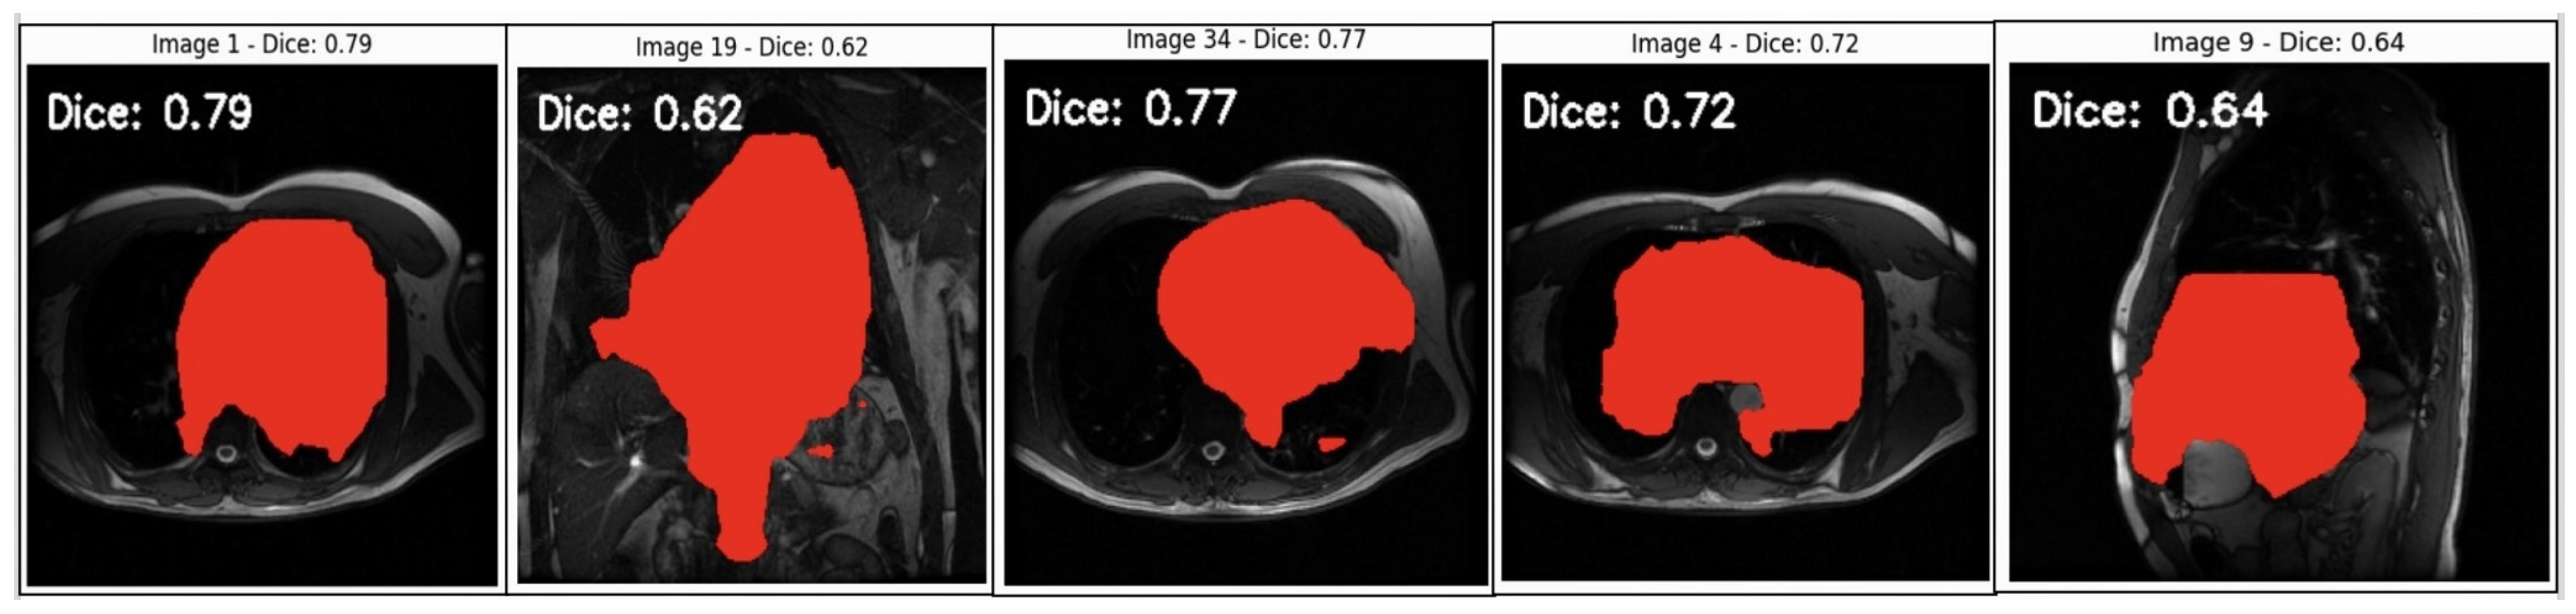

See a segmentation analysis of cardiovascular structures in MRI scans in Figure 6. MRI heart image segmentation masks were overlaid on MRI scans, with each image annotated with a Dice coefficient score. The Dice coefficient, a measure of overlap between the predicted segmentation mask and the ground truth mask was used to evaluate the accuracy of the segmentation models, with values closer to 1 indicating better overlap and thus higher segmentation accuracy.

• High Dice Scores (0.77–0.79): In images with Dice scores close to 0.8 (e.g., Image 1 and Image 34), the model demonstrated a high degree of overlap between the predicted mask and the ground truth. This suggests the model effectively captures the boundaries of the target structure within these particular scans. Higher Dice scores in these cases indicate that the segmentation model can accurately recognise and delineate the relevant cardiovascular structures when the images are clear and relatively uniform.

• Moderate Dice Scores (0.62–0.72): Images with Dice scores in the 0.6 to 0.7 range show moderate segmentation quality, suggesting some discrepancies between the model’s predicted mask and the ground truth. This could indicate challenges with variations in image intensity, complex anatomy, or partial occlusions within the image that reduce the model’s ability to accurately match the ground truth. These scores highlight areas where the segmentation model might need improvement to accurately handle complex or varied anatomical features.

• Lower Dice Scores (0.64 in Image 9): The relatively lower Dice scores, such as in Image 9 (Dice = 0.64), suggest that the model struggles with certain image features. This lower score could be due to image noise, non-standard anatomy, or limitations in the training data that hinder the model’s generalisability. Lower Dice scores in such images highlight the need for model improvement, such as training on a more diverse dataset or fine-tuning model parameters to enhance robustness.

The variation in Dice scores across different images indicates potential biases or limitations in the model’s current form.

• Inconsistent Dice scores across different images reveal a potential algorithmic bias, where certain image characteristics (e.g., intensity variations, anatomical differences, etc.) affect the model’s performance. A fair AI-driven diagnostic tool must perform equally well across diverse patient demographics and imaging conditions. These results suggest that the model needs additional training on a broader range of images to mitigate biases and improve generalisation across varied cases.

• For fair and reliable diagnostics, high segmentation accuracy is critical. The images with lower Dice scores indicate cases where the model fails to accurately capture cardiovascular structures, which could lead to missed or inaccurate diagnoses. Improving the segmentation performance, particularly in challenging cases, will enhance the tool’s diagnostic reliability.

• These results underscore the need for targeted model enhancements, such as incorporating more diverse training data using advanced augmentation techniques or fine tuning hyperparameters. By addressing the weaknesses indicated by lower Dice scores, the model becomes more robust, thus ensuring fairer and more accurate diagnostic outcomes.

Achieving consistent, high Dice scores across all cases will be instrumental in mitigating algorithmic bias and advancing the development of a fair and effective AI-driven diagnostic tool for cardiovascular imaging.